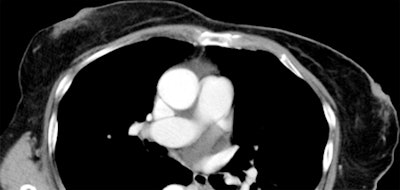

Salavatore's group conducted a pilot study comparing radiologists' readings of breast density at CT of the chest with breast density readings from mammography performed in the same patient (Radiology, October 14, 2013).

The study included mammograms and chest CT scans acquired within one year of each other in 206 women, between 2007 and 2011. Two radiologists reviewed the mammograms and CT scans and classified each case into one of the four breast density types defined by BI-RADS.